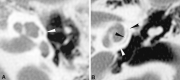

Background and purpose: Recent advances in the display of medical images permit the routine study of temporal bone CT images at high magnification. We noted an unfamiliar structure, which we now call the "cochlear cleft," in the otic capsule. To our knowledge, this report represents the first description of this structure in the medical imaging literature.

Conclusion: We describe a cleft in the otic capsule that is frequently seen on magnified images of temporal bone CT studies in children. The cleft may be the fissula ante fenestram.